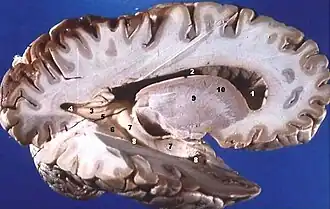

La substance grise est la partie des tissus du système nerveux central composée essentiellement des corps cellulaires et de l'arbre dendritique des neurones ainsi que de certaines cellules gliales. Au microscope, la substance grise apparaît plus sombre que le reste du tissu nerveux, dit substance blanche, qui est essentiellement constitué des faisceaux de fibres axonales gainées de myéline, à la couleur blanchâtre.

Dans l'encéphale, la substance grise est située en périphérie, c'est-à-dire autour de la substance blanche. De ce fait, on dit que la substance grise définit un cortex (« écorce » en latin). Ce cortex est formé d'un empilement de couches de cellules nerveuses (entre 3 et 6 pour le cortex cérébral et 3 pour le cortex cérébelleux) lesquelles se différencient par le type cytoarchitectonique, la densité cellulaire et la connectivité. Autour des ventricules cérébraux, la substance grise est agglutinée en amas cellulaires qui n'ont généralement pas l'organisation laminaire des cortex : ce sont les noyaux gris centraux (thalamus, ganglions de la base, etc.).